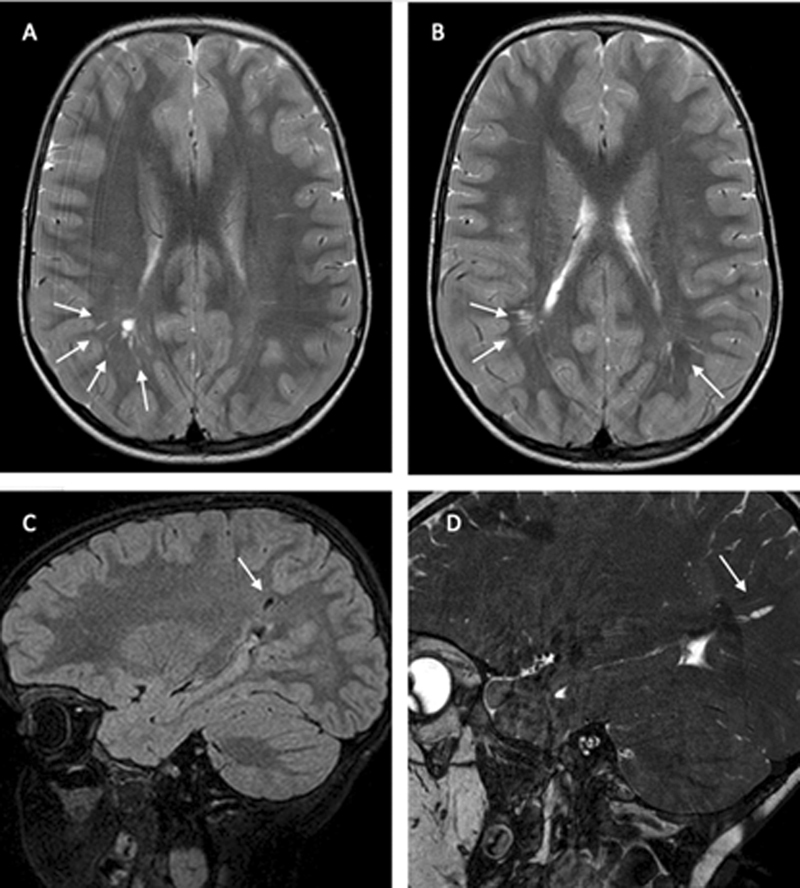

Abstract Image